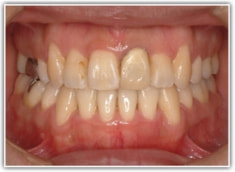

治療前

治療後(2年3ヶ月後)

修復歯、補綴歯もあります。下顎8番が水平埋伏しています。